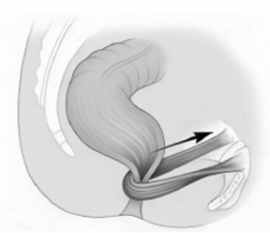

Αποτελεί τη συστροφή του εντέρου γύρω από τον άξονα του μεσεντερίου του και αφορά συχνότερα το σιγμοειδές (65%) και το τυφλό. Οι καταστάσεις που προδιαθέτουν σε συστροφή σιγμοειδούς είναι: (1) πλεονάζον, μεγάλου μήκους σιγμοειδές, (2) μακρύ μεσοσιγμοειδές με στενή βάση και (3) υψηλό φορτίο κοπράνων λόγω βαρείας, χρόνιας δυσκοιλιότητας. Συχνότερα…